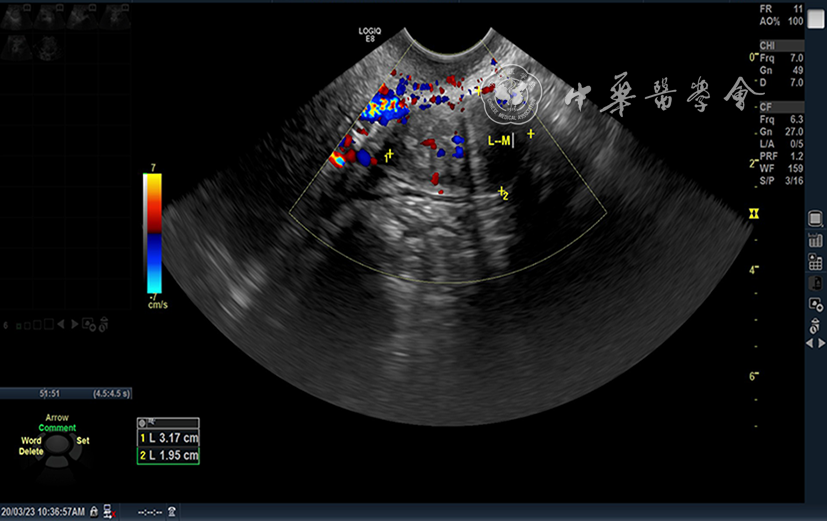

图2 2020年3月23日超声检查显示左侧附件区低回声团块,与2020年3月18日超声检查图像无明显差异